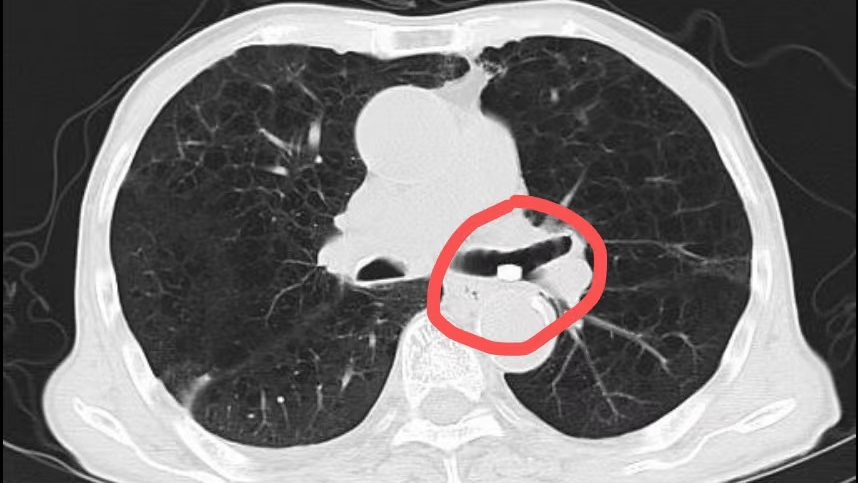

1例"特殊"的吸入性肺炎

患者刘爷爷因误吸药丸出现呛咳,气促紧急入院,胸部ct显示,左下叶支